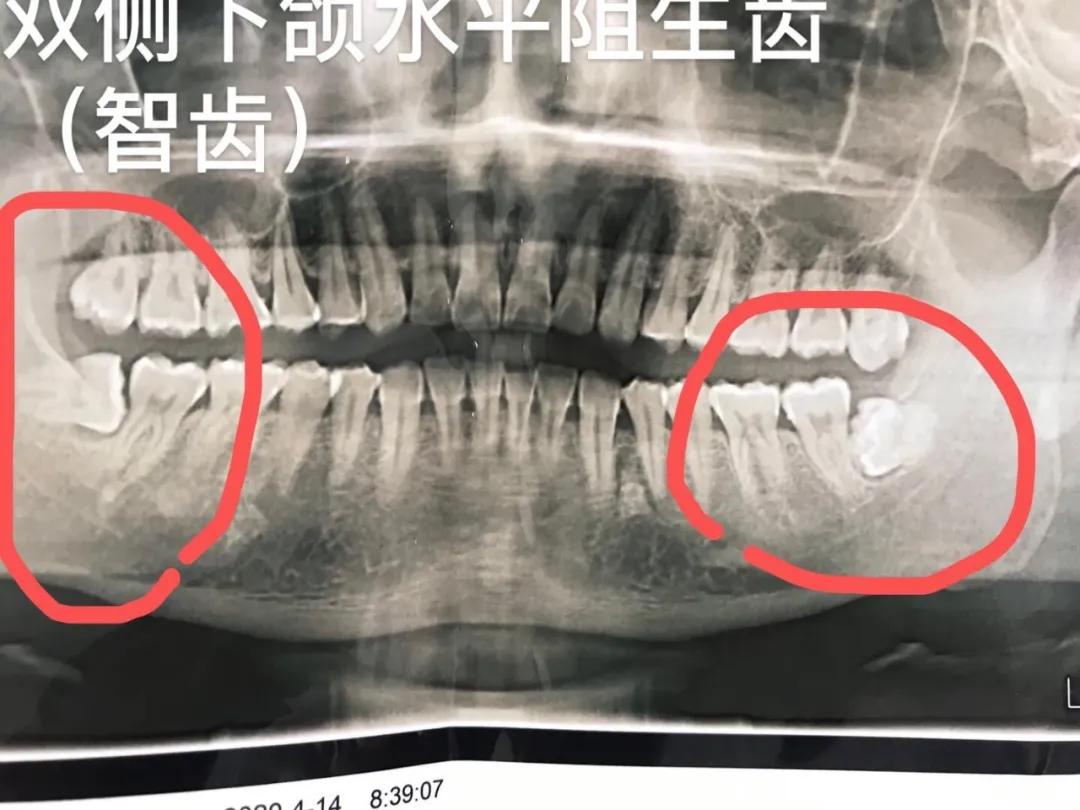

3.各类阻生牙(智齿)、儿童埋伏牙,复杂牙等疑难牙齿的微创拔除。治疗效果显著。